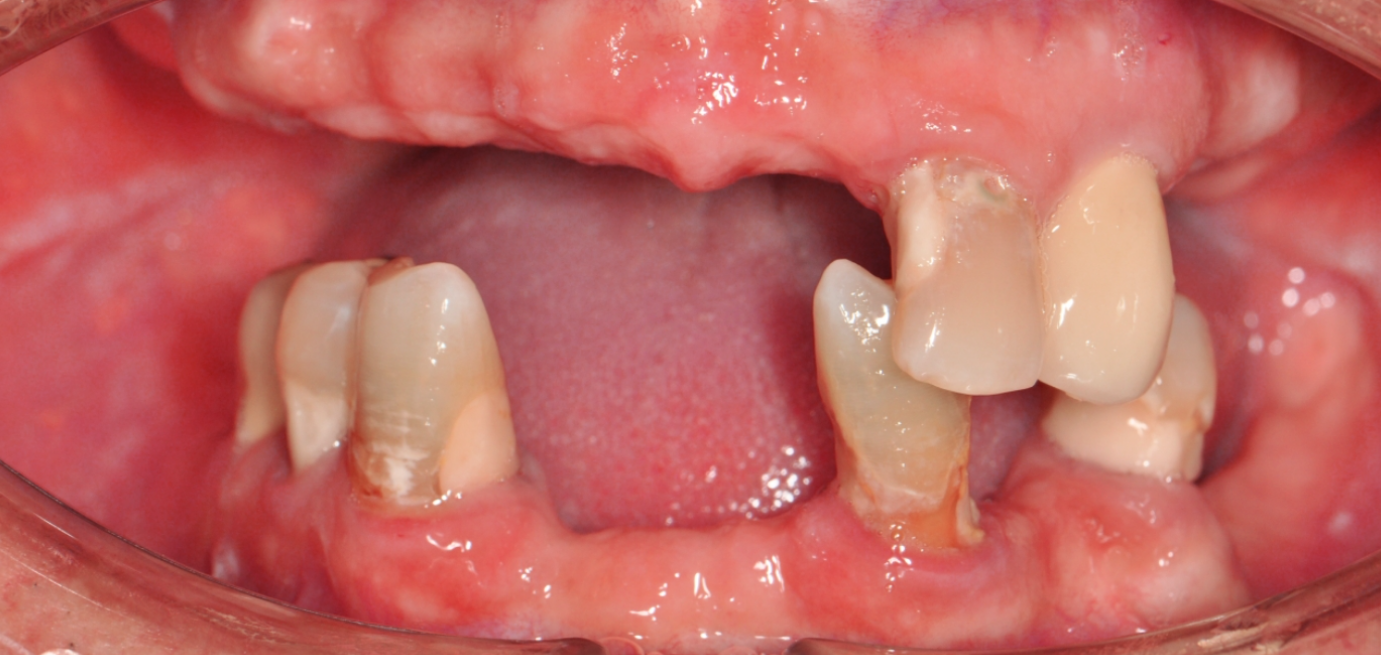

Before & After

Drag Before After

버튼을 움직여서 변화를 확인해보세요.